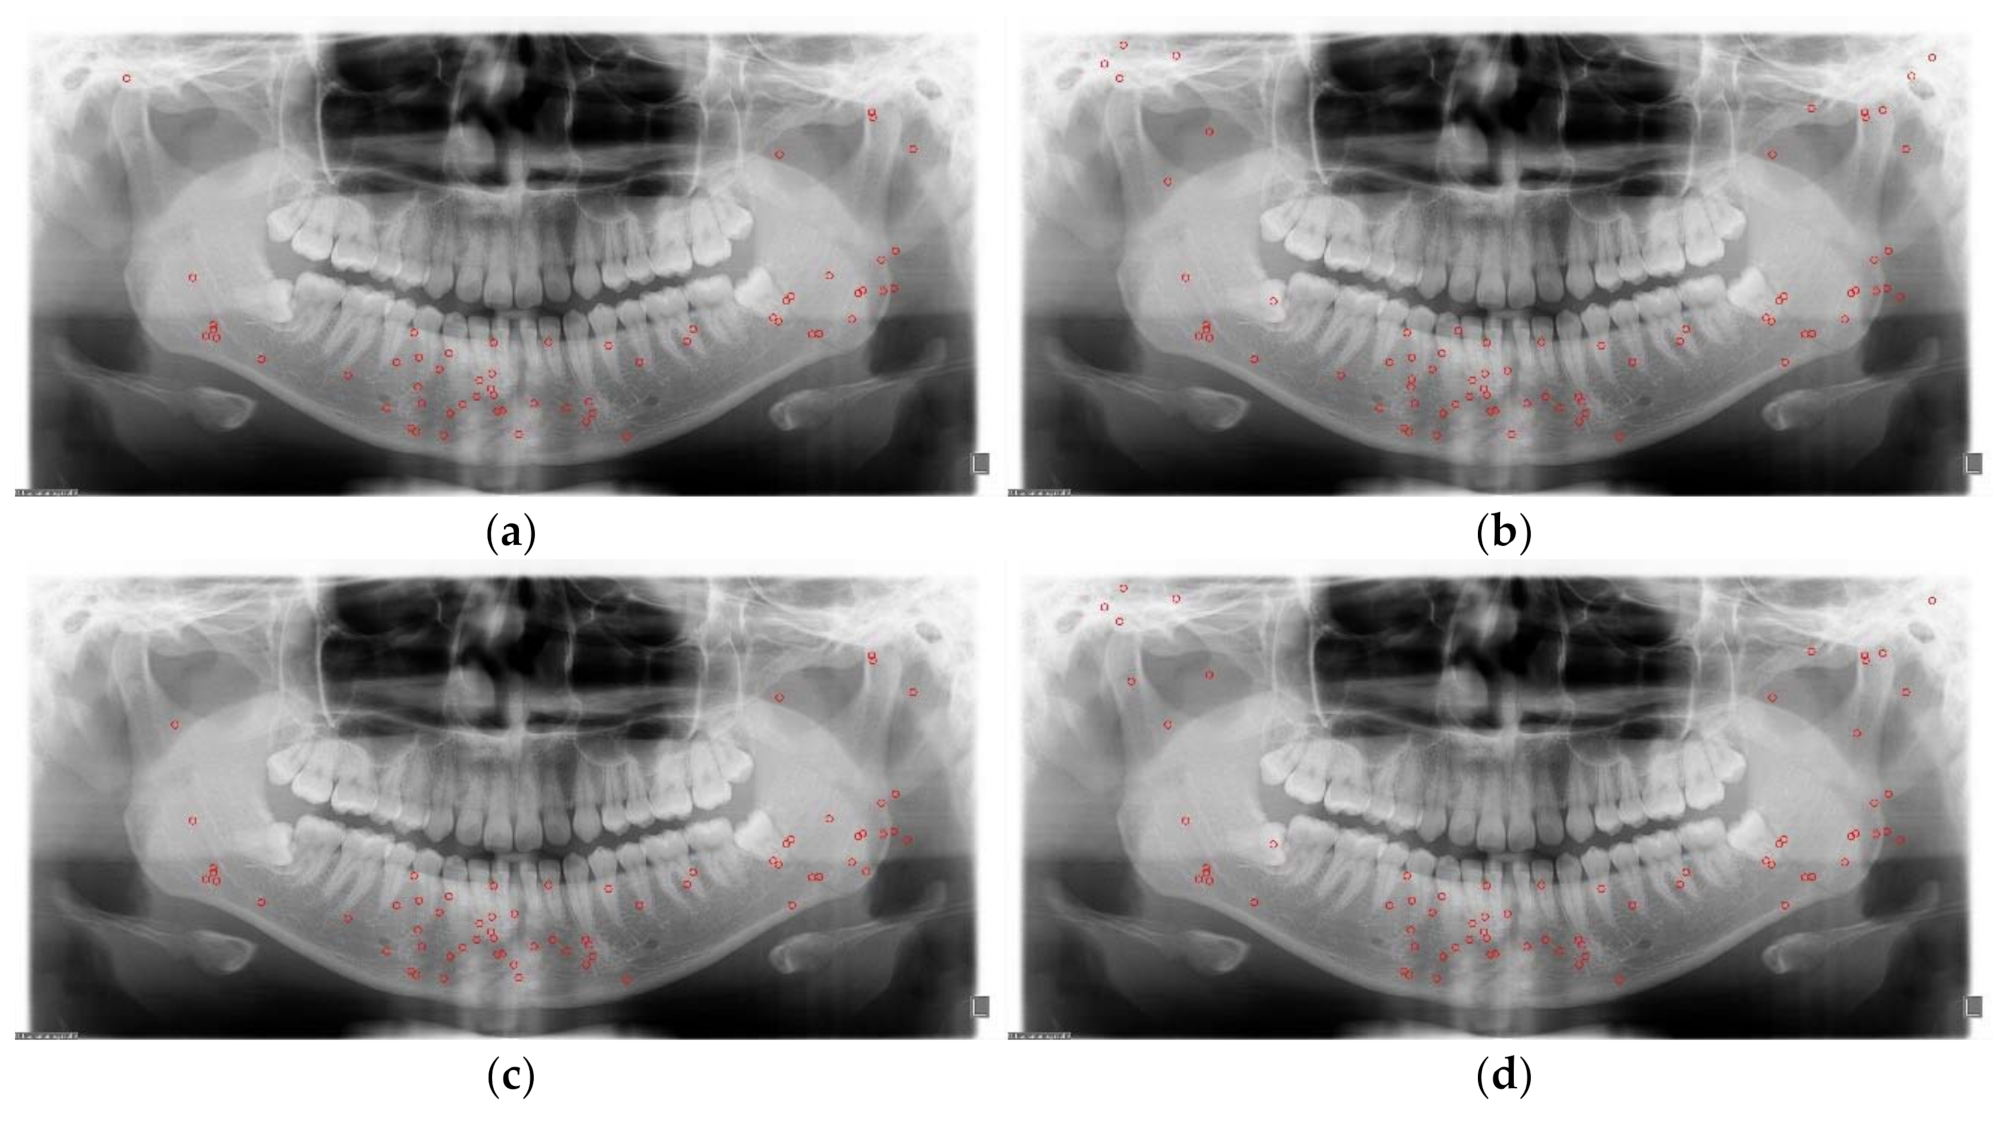

2.2.1. Data Augmentation

3.2. Detection Results